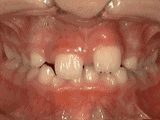

第一鐘---

前牙移位,因為有牙齒缺失,導(dǎo)致相鄰牙齒開始沒有秩序的前突,經(jīng)過矯正后是變成這樣的~